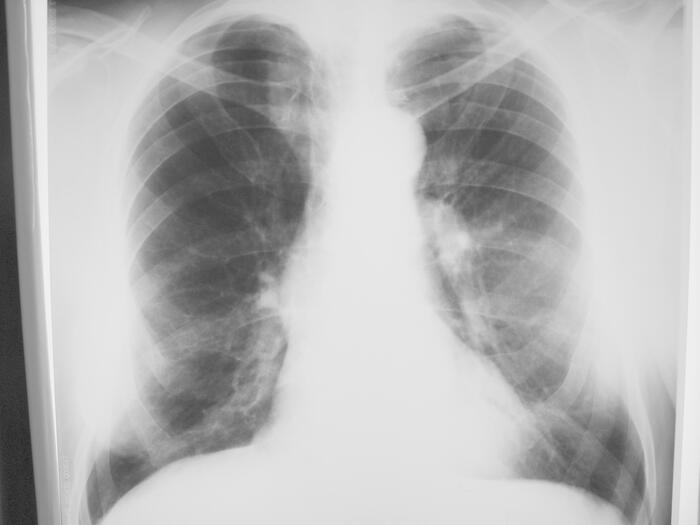

Расшифровка цифровых кодов флюорографии с примерами

19 - Изменения диафрагмы, не связанные с плевральной патологией (диафрагмальная грыжа, высокое стояние диафрагмы и т. д.).